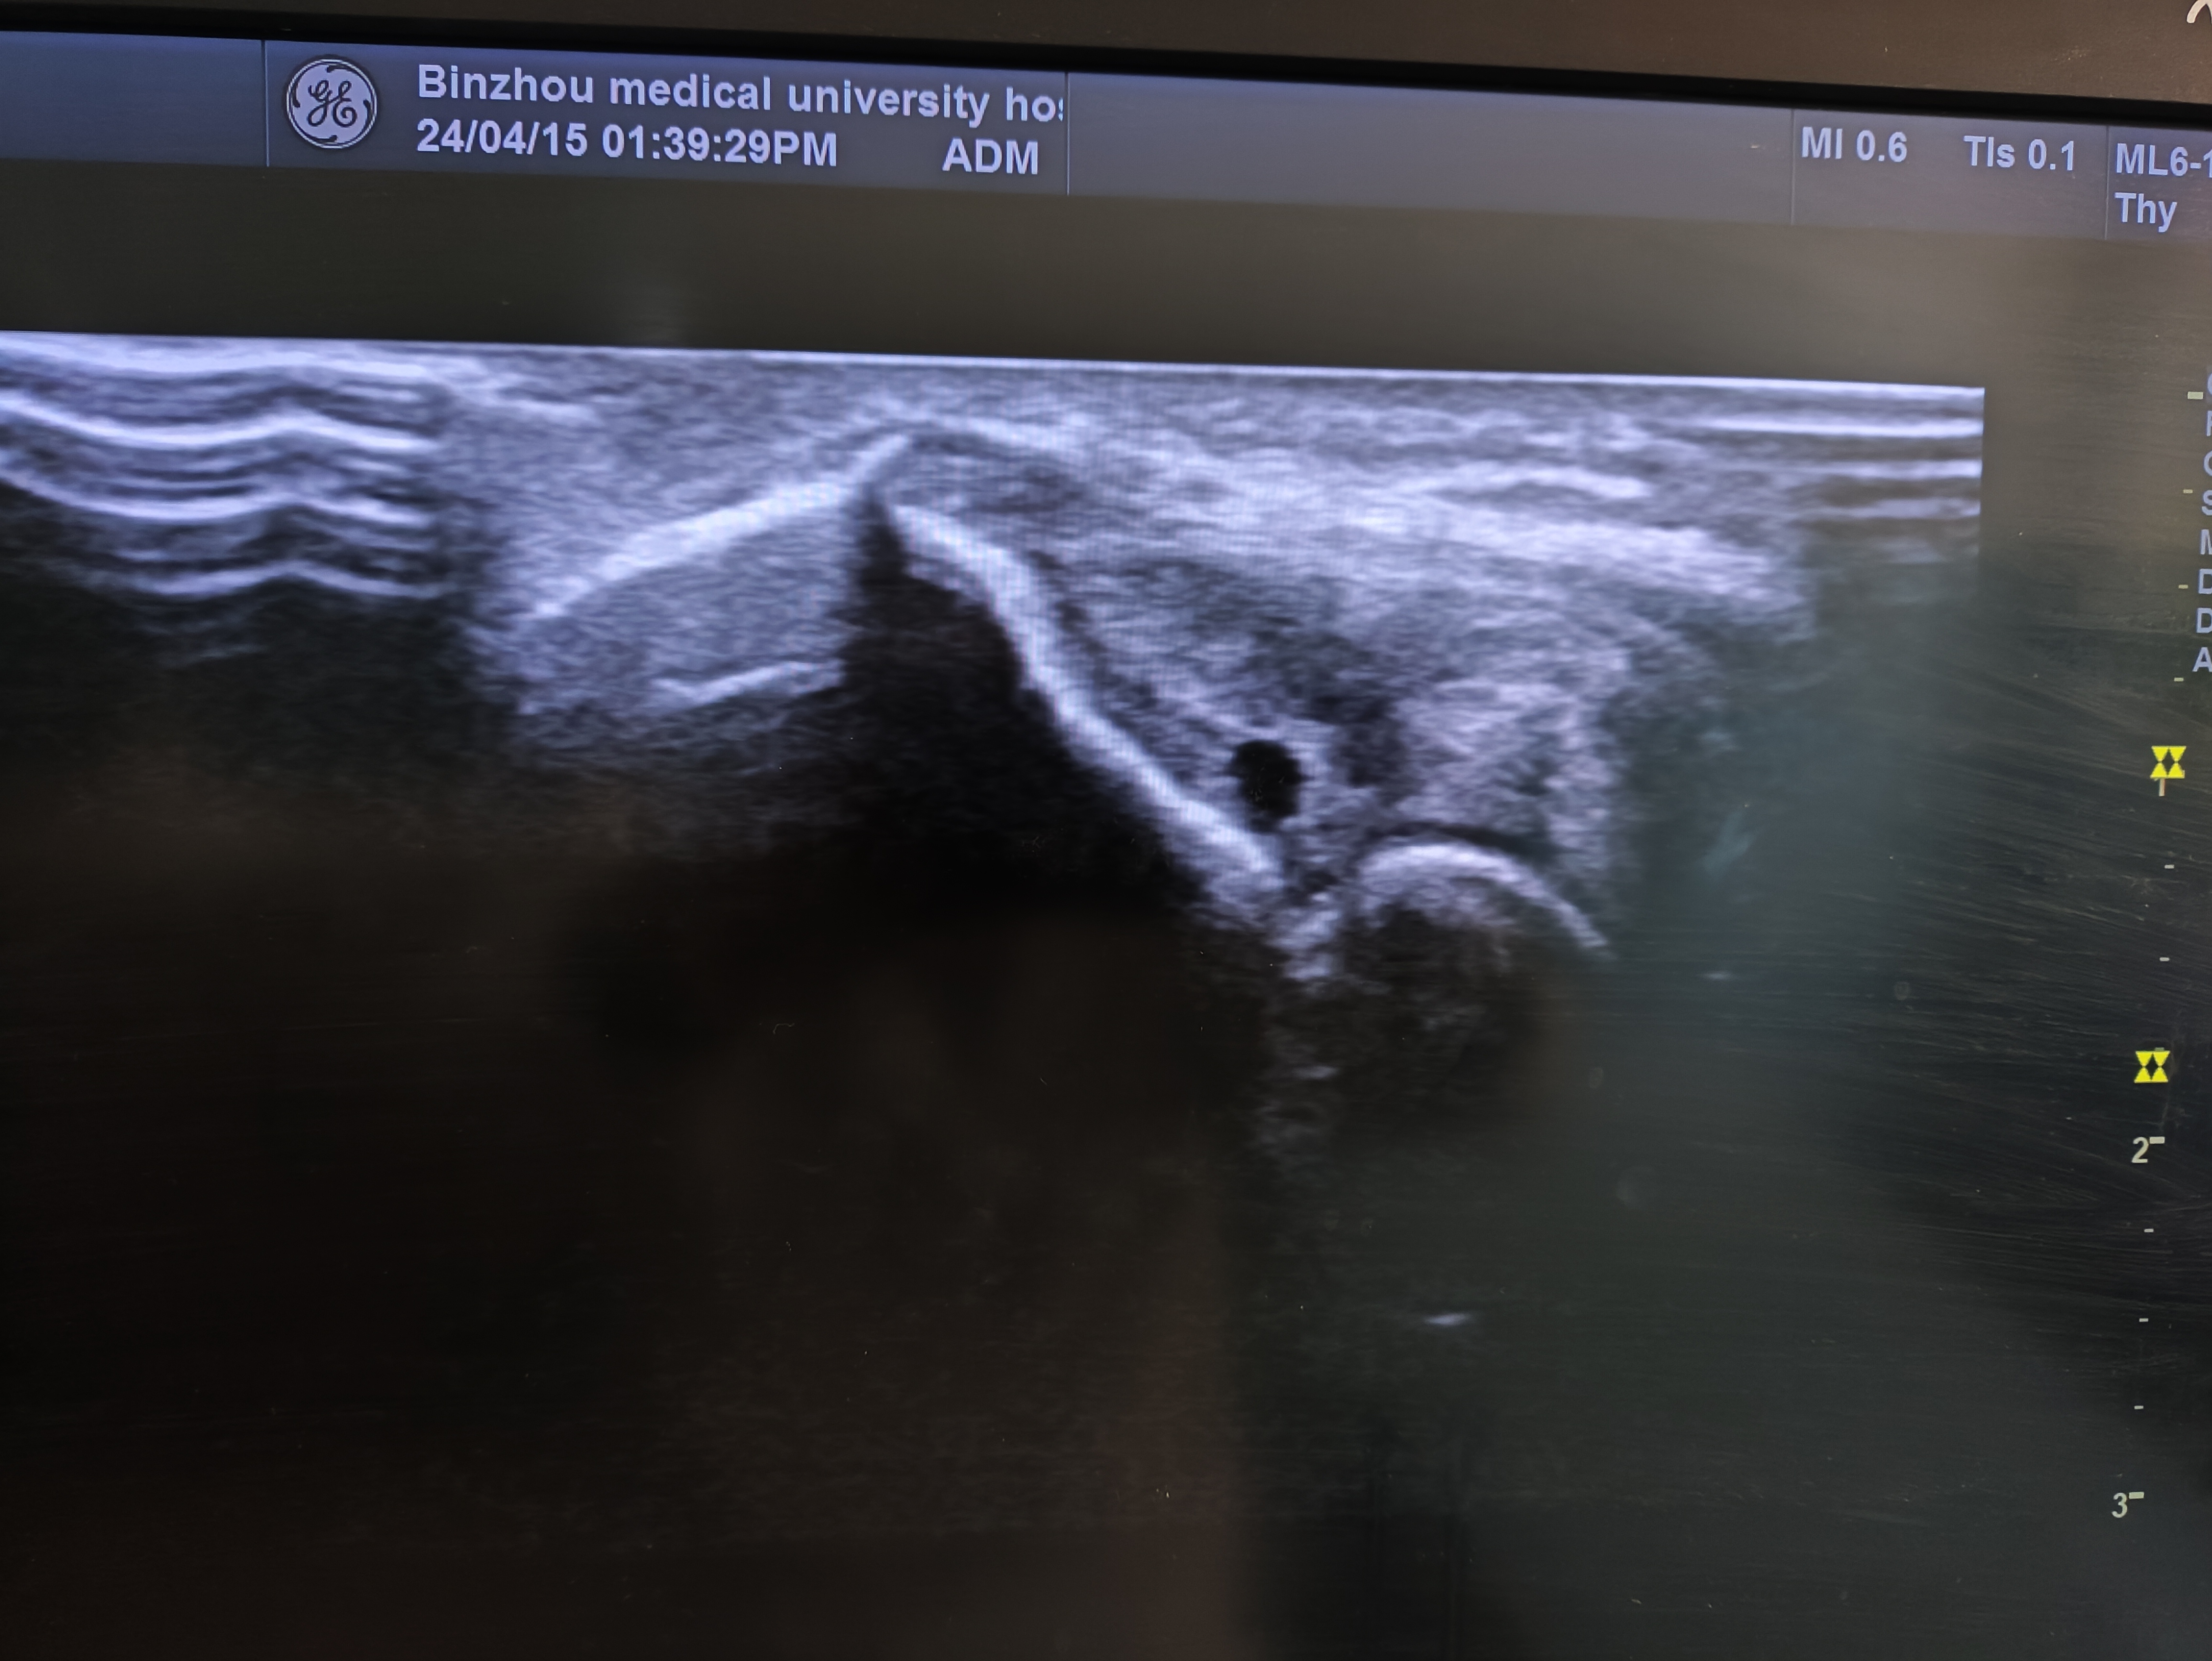

經(jīng)常碰到一些孕婦,進門后大汗淋漓,喘的很厲害的說:“大夫,我這活動的好久了,應(yīng)該能看清楚了吧!”不知何時,興起了產(chǎn)檢前吃巧克力,喝糖水,爬樓梯,跑跳等各式各樣的所謂的增加胎兒活動的行為。當(dāng)孕婦告知時搞得我們哭笑不得。在做三維、四維,胎心,以及NT檢查時,經(jīng)常因為胎兒胎位不合適,不利于檢查,檢查醫(yī)師會要求孕婦出去活動一會,期待胎兒能夠轉(zhuǎn)到合適胎位,顯示感興趣區(qū)域,這種情況,我們只能是多次檢查多做幾次,看看能否碰到合適體位。孕婦有的著急,還會拍打胎兒,跑跳,這些行為是沒有意義的,在檢查之前做這些動作更是毫無意義,有可能讓本來安靜的體位合適的胎兒變得躁動,不利于超聲檢查,望周知。